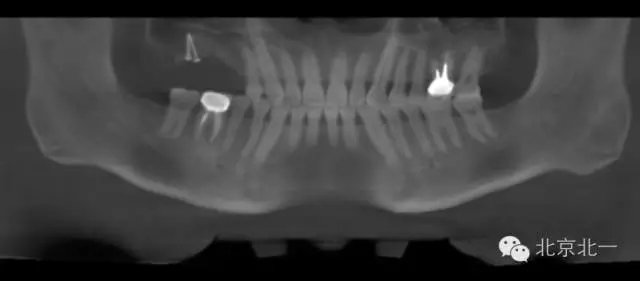

圖二:手術(shù)前全景片

圖十七:縫合。非潛入

圖二十-二十二:ONLAY植骨半年后

圖二十三:種植后當(dāng)天全景片。